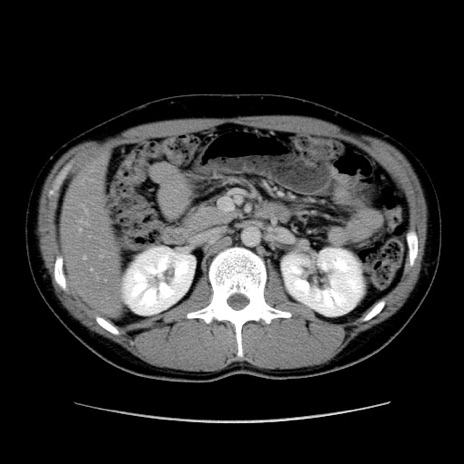

症例36(横断像)

【症例】20歳代 男性

【主訴】心窩部痛

【現病歴】今朝より上腹部痛あり。一旦軽快していたが再度出現したため救急要請。昨日夕に白身の魚を含む刺身を食べた。

【身体所見】BP 136/89mmHg、HR 74/min、BT 37.0℃、腹部:膨満、軟、心窩部に圧痛あり。反跳痛なし、筋性防御なし、腸雑音やや亢進あり。

【データ】WBC 17700、CRP 0.48